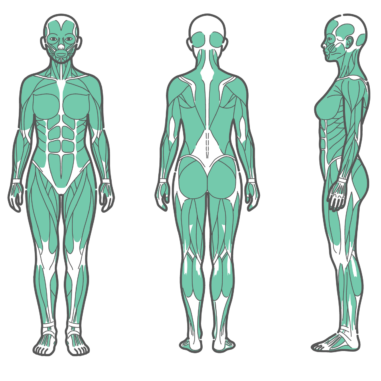

上半身・体幹 女性の全身筋肉図・人体解剖図のイラストセット(正面・背面・側面)